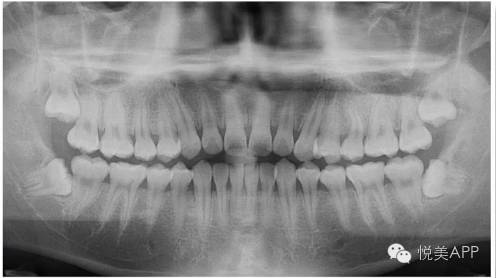

2、拍一张头颅的X光片——

4、拍一张口腔的曲面断层全景片——能够一比一的复制出下颌角的下颌骨状况,还能看到神经管和神经孔,这个片子大家很熟悉啊,有时候治疗牙根也会拍。

人体的下颌骨中有一个非常重要的解剖结构,叫做下齿槽神经血管,它在哪里呢?它就在下颌骨的里面沿线走~

曲面断层中也能看到——